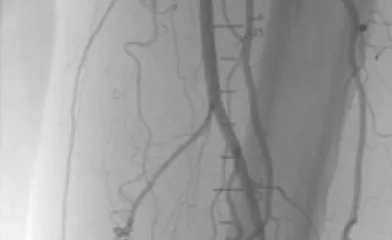

ケースレポート実際の臨床応用を通じて、製品への理解をさらに深めてください。 製品に関連するケースレポートをご覧ください並び替え昇順降順並び替え 昇順降順ポートフォリオ大動脈領域末梢血管領域ポートフォリオ 大動脈領域末梢血管領域関連製品ゴア® TAG® コンフォーマブル 胸部大動脈ステントグラフト アクティブコントロールシステムゴア® エクスクルーダー® IBEゴア® エクスクルーダー® コンフォーマブル AAAステントグラフト アクティブコントロールシステムゴア® バイアバーン® VBX バルーン拡張型ステントグラフト ゴア® バイアバーン® ステントグラフト関連製品 ゴア® TAG® コンフォーマブル 胸部大動脈ステントグラフト アクティブコントロールシステムゴア® エクスクルーダー® IBEゴア® エクスクルーダー® コンフォーマブル AAAステントグラフト アクティブコントロールシステムゴア® バイアバーン® VBX バルーン拡張型ステントグラフト ゴア® バイアバーン® ステントグラフト治療領域末期腎不全末梢血管疾患胸部大動脈疾患腹部大動脈瘤血管損傷治療領域 末期腎不全末梢血管疾患胸部大動脈疾患腹部大動脈瘤血管損傷 34 結果 Image 6 Fr 対応ゴア® バイアバーン® VBXバルーン拡張型ステントグラフトを用いた橈骨動脈アプローチによる腸骨動脈 EVTの一例 さらに詳しくImage AVGの人工血管延長術後に生じた再流出路狭窄症例に対してゴア® バイアバーン® ステントグラフトを挿入した一例 さらに詳しくImage DESによる左浅大腿動脈の慢性閉塞の治療後、コロナ禍の受診中断でステント内閉塞となり再来された一例 さらに詳しくImage SFAの長区域閉塞病変にゴア® バイアバーン® ステントグラフトを留置し、3年フォローした一例 さらに詳しくImage SFA入口部からの長区間超高度石灰化閉塞病変に対して外科的内膜摘除術との併用でゴア®バイアバーン® ステントグラフトを留置し、6か月フォローした一例 さらに詳しくImage SFA起始部のランディングに悩むCTO病変に対しゴア® バイアバーン® ステントグラフトを用いてEVTを完遂し、2年経過を観察した一例 さらに詳しくImage Shaggy Aortaを合併した遠位弓部大動脈瘤に対するTEVAR さらに詳しくImage ケースレポート:ゴア® TAG® コンフォーマブル 胸部大動脈ステントグラフト アクティブコントロールシステム さらに詳しくImage ケースレポート:ゴア® エクスクルーダー® IBE さらに詳しくImage ケースレポート:ゴア® バイアバーン® VBX バルーン拡張型ステントグラフト さらに詳しくImage ケースレポート:ゴア® バイアバーン® ステントグラフト さらに詳しくImage ケースレポート:外傷性胸部大動脈損傷に対するゴア® TAG® コンフォーマブル 胸部大動脈ステントグラフト アクティブコントロールシステムの有用性 さらに詳しくImage ゴア® TAG® コンフォーマブル 胸部大動脈ステントグラフト アクティブコントロールシステムの特徴および有用性 さらに詳しくImage ゴア® バイアバーン® ステントグラフトの使い所 –長期開存したISO症例– さらに詳しくImage ゴア® バイアバーン® ステントグラフトを人工血管内シャント静脈側吻合部狭窄のリコイルに対して用いた症例 さらに詳しく さらに表示 トップ